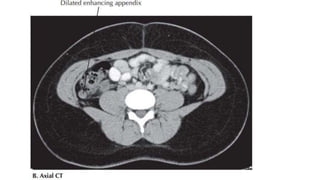

• КТГ, МРТ

Оношлогоо • Асуумж:Зовуурь, өвдөлтийн эхлэл, анх өвдсөн байрлал, өвдөлтийн шилжилт. Эм тариа хэрэглэсэн байдал • Бодит үзлэг: ерөнхий болон хэсгийн үзлэг, эрхтэн тогтолцооны үзлэг. Уруул омголдсон, хэл өнгөртсөн. Хэвлийн өнгөц болон гүний тэмтрэлтээр хэвлийн баруун доод хэсэгт эмзэглэлтэй. Бодит үзлэгээр мухар олгойн үрэвслийн үед илрэх өвөрмөц эмнэл зүйн шинжүүдийг илрүүлэх • Шаардлагатай бол шулуун гэдэс, үтрээний үзлэг. • Шинжилгээ: Цусны шинжилгээнд – лейкоцитоз, гранулоцитоз, цагаан эсийн зүүний хазайлт, СОЭ ихсэх • Хэвлийг гэрэлд тойм харах – мухар гэдэс орчимд хий их үүссэн байна. • ЭХО – зарим тохиолдолд мухар олгой харагдаж болно. Хэвлийн хөндий бага аарцагтүрэвслийн шүүдэс байгаа эсэх. Олгойн нэвчдэс байгаа эсэхийг магадлах • КТГ, МРТ